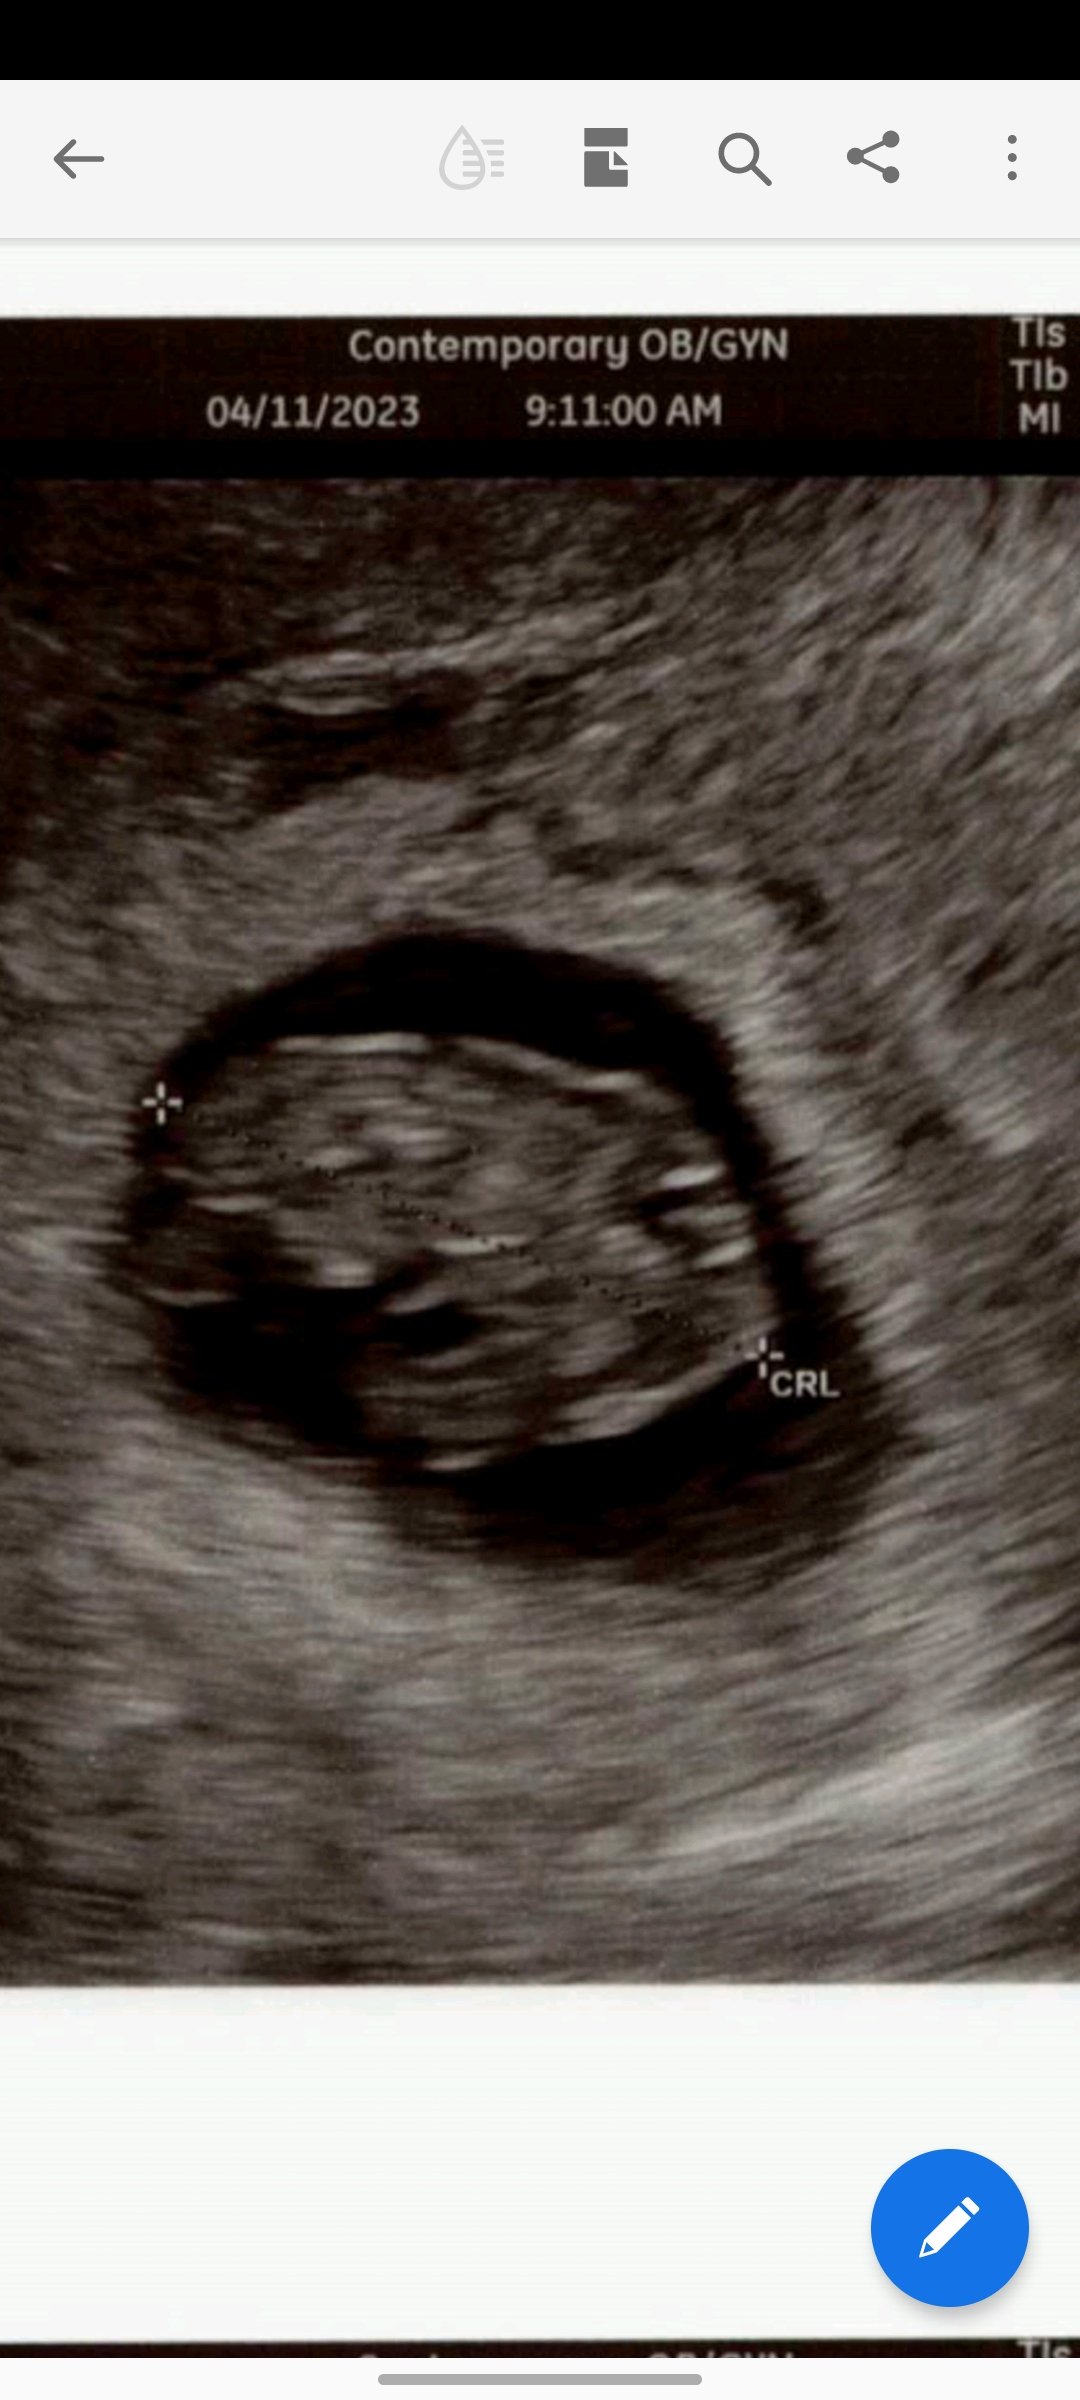

I have had three early miscarriages and at least two were blighted ovums so I was not expecting a positive test and DEFINITELY wasn’t expecting to see a heartbeat but here we are holding strong at 6 weeks 2 days!

Still early so with my history I’m not out of the woods but I have never seen a baby or heartbeat in my previous pregnancies, so I am very cautiously optimistic.